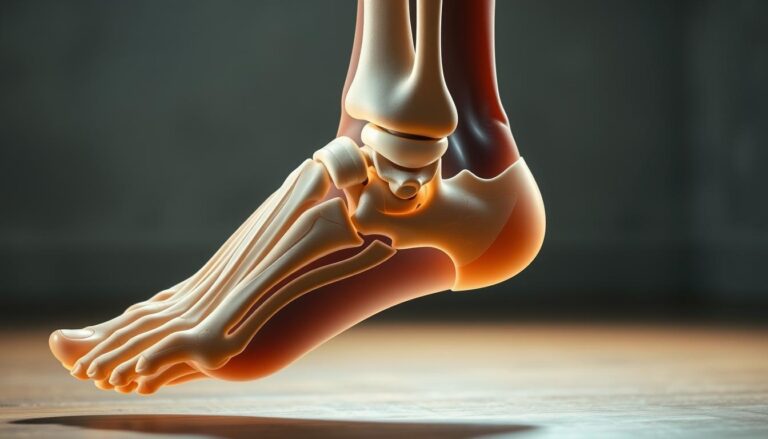

Mięsień strzałkowy czwarty i „niski” brzusiec mięśnia strzałkowego krótkiego a niestabilność funkcjo

Czy jesteś pewien, że znasz wszystkie aspekty anatomiczne mięśni strzałkowych, które mogą wpływać na…